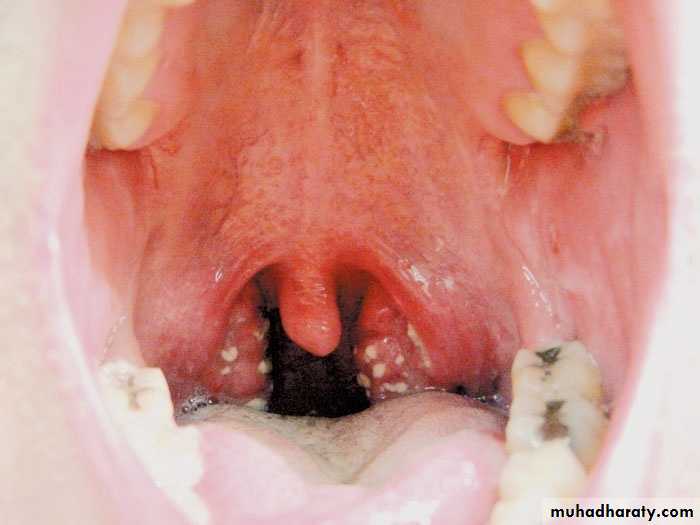

Herpes zoster